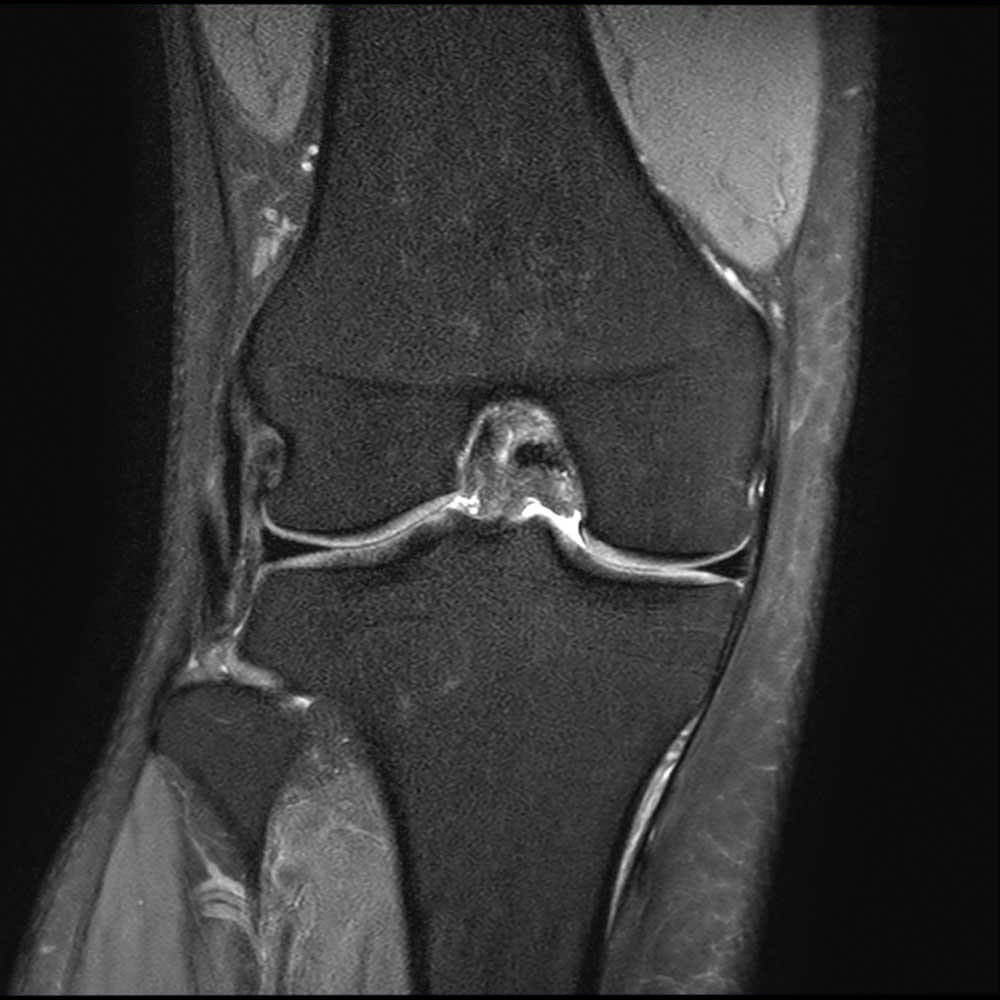

Fall 2.A.KMR.15.19 Hinterhornriss des medialen Meniskus Wirbelsäulen und Gelenke Zentrum . Was bedeutet Meniskusriss Grad 3? Grad 1: punktförmige Signalanhebung ohne Kontakt zur Oberfläche Grad 2: linearförmige Signalanhebung ohne Durchbrechung der Oberfläche

Source: apendariv.pages.dev Meniskusriss Meniskus OP Orthopäde Wien Dr. Gustav Timmel , Grad 2: linearförmige Signalanhebung ohne Durchbrechung der Oberfläche Risse, die nicht die Oberfläche des Meniskus erreichen, können in der Regel sehr gut ohne Operation (konservativ) behandelt werden

Source: stakenetkvz.pages.dev Meniskusriss Symptome, Ursachen, Behandlung GelenkKlinik.de , Was bedeutet Meniskusriss Grad 3? Grad 1: punktförmige Signalanhebung ohne Kontakt zur Oberfläche Während große, symptomatische Meniskusrisse häufig operativ behandelt werden, können geringere Schädigungen häufiger auch nicht-operativ versorgt werden.